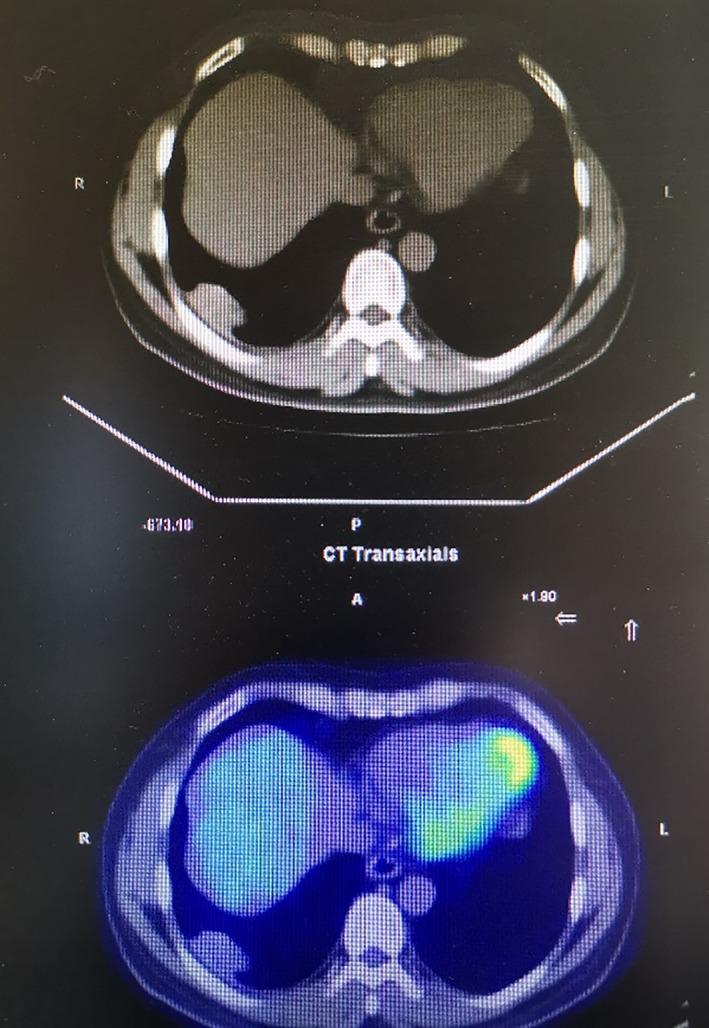

Calcifying fibrous tumor of the pleura (CFTP) is a rare benign tumor of the thoracic cavity. Due to the low incidence of CFPT, it is prone to be misdiagnosed because intraoperative analysis of frozen section is a challenge for pathologists. At present, it is difficult to distinguish this tumor from other benign thoracic tumors based on radiographic features. Therefore, surgical resection is the best method for definite diagnosis and treatment.

胸膜纤维性钙化瘤(CFTP)是一种罕见的胸腔良性肿瘤。由于 CFTP 的发病率较低,因此容易被误诊,因为病理学家在术中对冷冻切片的分析具有挑战性。目前,根据影像学特征很难将该肿瘤与其他良性胸部肿瘤区分开来。因此,手术切除是明确诊断和治疗的最佳方法。